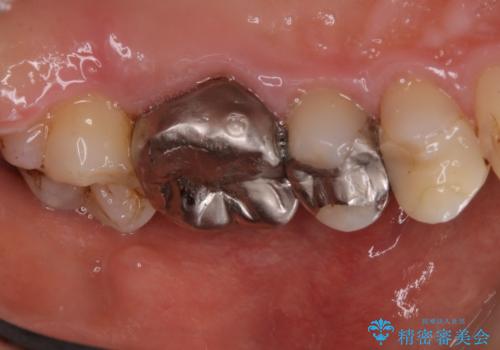

歯の表面に、茶色く色が残っている所がありますが、これは詰め物の変色の所と、虫歯になっている所です。以前に、CR(コンポジットレジン)による虫歯治療がされています。

CRは経年的劣化や、着色してしまうことがあります。PMTCでクリーニングを行うと、古いCRが目立つことがあるため、気になる際は詰め替えを行います。

茶色くなっている部分が、着色なのか、劣化なのか、虫歯によるものなのかは判別が難しいことがあります。そのため、定期的にPMTCを行うことで状態の確認が的確に行えます。